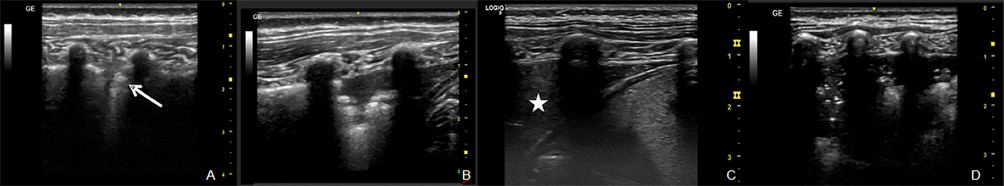

• Patrones ecográficos: el pulmón normal no se visualiza directamente, pero en las consolidaciones (donde el alveolo está relleno de exudado o líquido) alteran la impedancia y se hacen visibles siempre que contacten con la pleura, lo que ocurre en > 95 % de las neumonías pediátricas. La imagen típica es una zona hipoecoica subpleural con distintos patrones (Fig. 7):

Figura 7. Patrones ecográficos en neumonía: A. Líneas B perilesionales y márgenes imprecisos (flecha). B. Signo del desgarro (shred sign). C. Hepatización pulmonar (estrella). D. Broncograma aéreo dinámico.

– Líneas B perilesionales y márgenes imprecisos en condensaciones pequeñas.

– Signo del desgarro (shred sign): borde irregular entre zonas aireadas y consolidadas; suelen aparecer líneas B en la zona posterior a la consolidación.

– Hepatización pulmonar: con ecoestructura similar a la del hígado.

– Broncograma aéreo dinámico: puntos o líneas blancas móviles dentro de la consolidación que corresponde a la imagen del bronquio según el corte sea transversal o longitudinal.